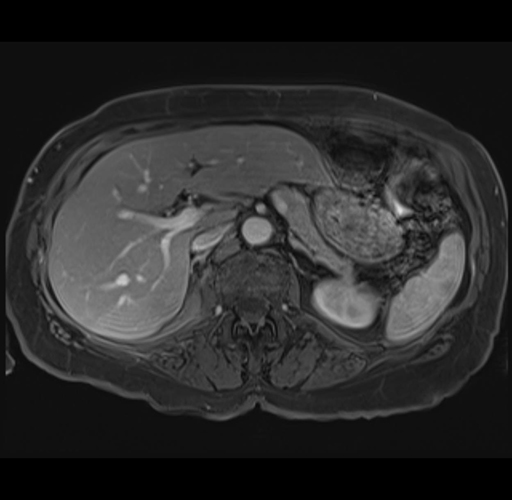

MRI T1

Imaging analysis